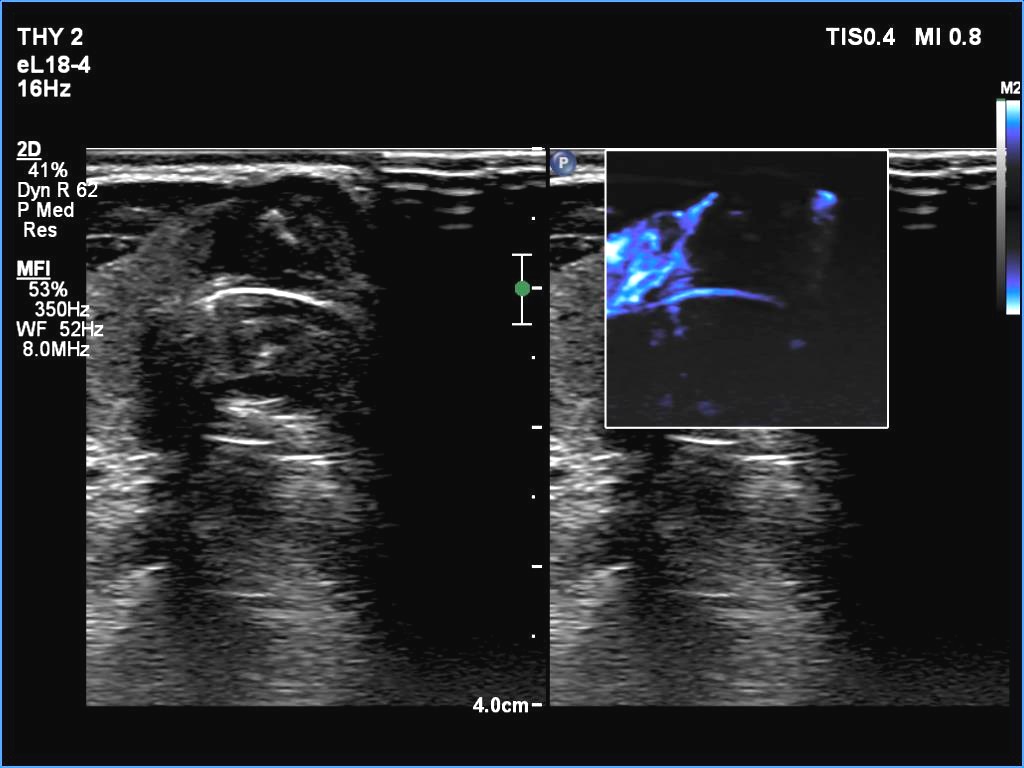

Right lobe, longitudinal scan

Isthmus, transverse scan, microflow imaging. The nodule has no vessels.